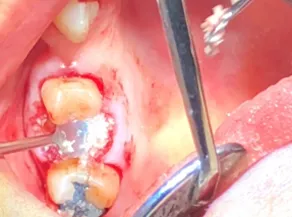

Atraumatic tooth removal and GBR procedures demand meticulous protocols. This course is dedicated to instilling a rock-solid foundation. We’ll cover early case selection, strategizing, step by step surgical protocols from sectioning to graft selection to suturing. Also, a complete blueprint from pre-op consents to post-op guidelines. Each day, we spend about ninety minutes in lecture, and the remainder of the day YOU are performing surgery. You can expect to perform five to six surgeries from a few complex teeth requiring flaps (doesn’t matter if you never laid a flap – that is why you are here), graft selection, membrane use, socket seals, PRF to Full mouth extractions.

- Employ Flap designs – 3 corner- 4 corner